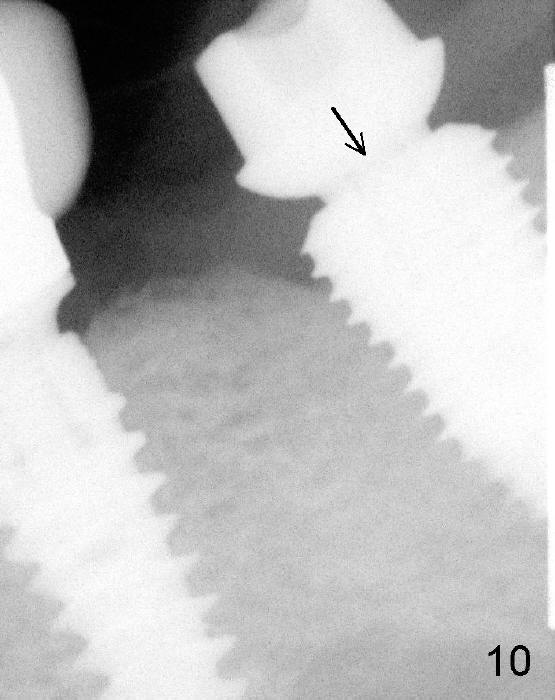

CBCT analysis reveals that there is an abnormal segment of the inferior alveolar nerve (IAN), slightly mesial to the site of #18. Intraop positional PA (Fig.1) shows that it is predictably safe to place 6.3x8 mm implant with the apical diameter (4.3 mm < 2.46 mmx2). Red dashed line indicates the abnormal segment of the IAN (pink line: normal segment). There is also some distance to IAN when 6x11 mm tap is inserted at the depth of 8 mm (Fig.2). Finally a 6.3x10 mm extra wide implant (Brushite) is placed with 3.88 mm from IAN (Fig.3).